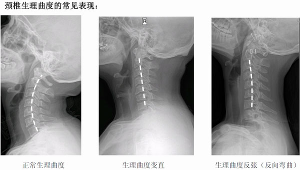

人體端坐或站立時,從側方看人的脖子似乎是直的,但包繞其內的頸椎並不是直的,而是在其中段有一向前凸出的弧度。這一向前的弧形凸起,

自然曲度髓、神經、血管等重要組織正常的解剖生理需要。每當外傷、退變姿勢不良時,不僅可以造成頸椎生理曲度的改變,而且可以因此引起相應的病理改變,從而出現臨床症狀及X線改變等。頸椎自然曲度的存在,能增加頸椎的彈性,減輕和緩衝重力的震盪,防止對脊髓和大腦的損傷。

如果某人的頸椎自然生理曲度變直,或者說是存在更進一步的損傷弧度消失,那么將會影響到頸椎對於頭部的減震作用。例如在乘車或是運動跳躍的過程中,頭部受到的衝擊作用將會更加明顯,容易出現脊髓和大腦的各種損傷。得頸部活動僵硬不自然,除了影響到自身的行動能力之外,還會影響美觀。